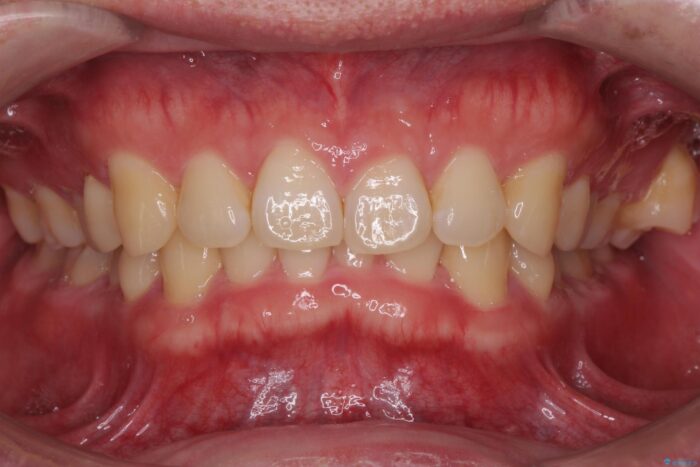

下の歯のがたつきが気になるとご来院されました。

左上の奥歯がシザーバイトがありました。

部分矯正を行いシザーバイトを改善した後、インビザラインで歯列を整えました。

シザーバイトは歯と歯が噛み合っていないのでしっかり噛めるように処置をする必要があります。

歯のがたつきが改善され大変お喜びいただけました。